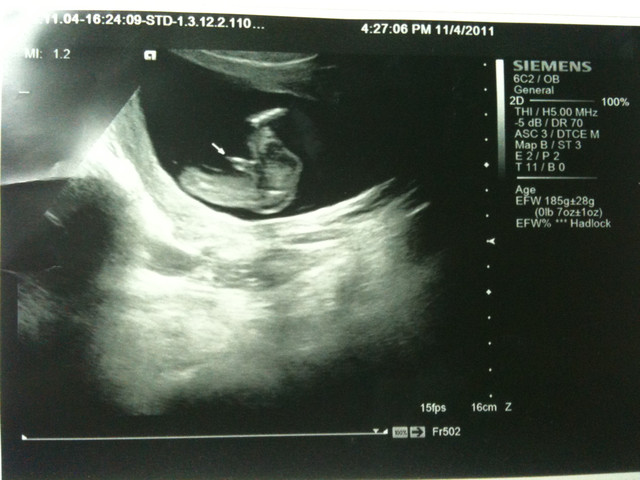

2011/11/4

第三次去產檢 確認上次抽血檢查結果

抽血結果:正常 有德國麻疹抗體

驗尿結果:膀胱有點發炎 開消炎藥改善

本次自費檢查第二孕期母血唐氏症篩檢 900 元

醫生公布小朋友性別: BOY

小朋友的身體狀況: 一切正常 大小約為17週大小(實際16週)

小朋友身高(頭到屁股):10 cm

箭頭所指處為小朋友的性別